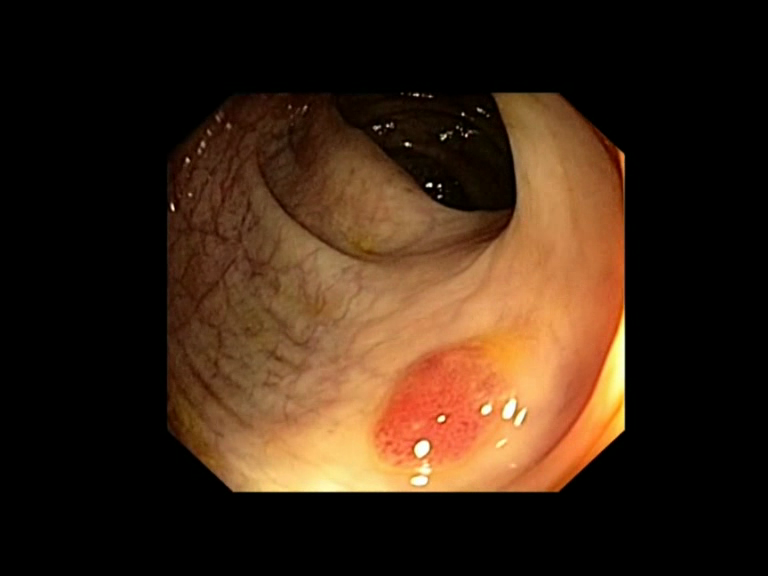

| Lesion | White Light Frame | NBI Frame | White Light Video | NBI Video | Camera Calibration |

| serrated_01 |  |

|

WL.mp4 | NBI.mp4 | cam.xml |